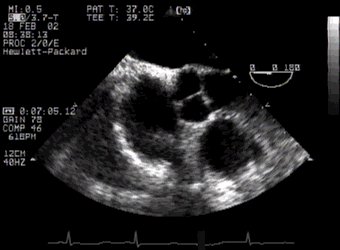

The principles of multiplane imaging are the same as for biplane imaging - the probe is simply a lot more convenient to use. Multiplane imaging has now become the standard. You will find that it's often difficult to cut anatomical structures such as the aortic valve at right angles with biplane imaging. Compare the following two images:

CLICK FOR VIDEO: aortic valve short axis